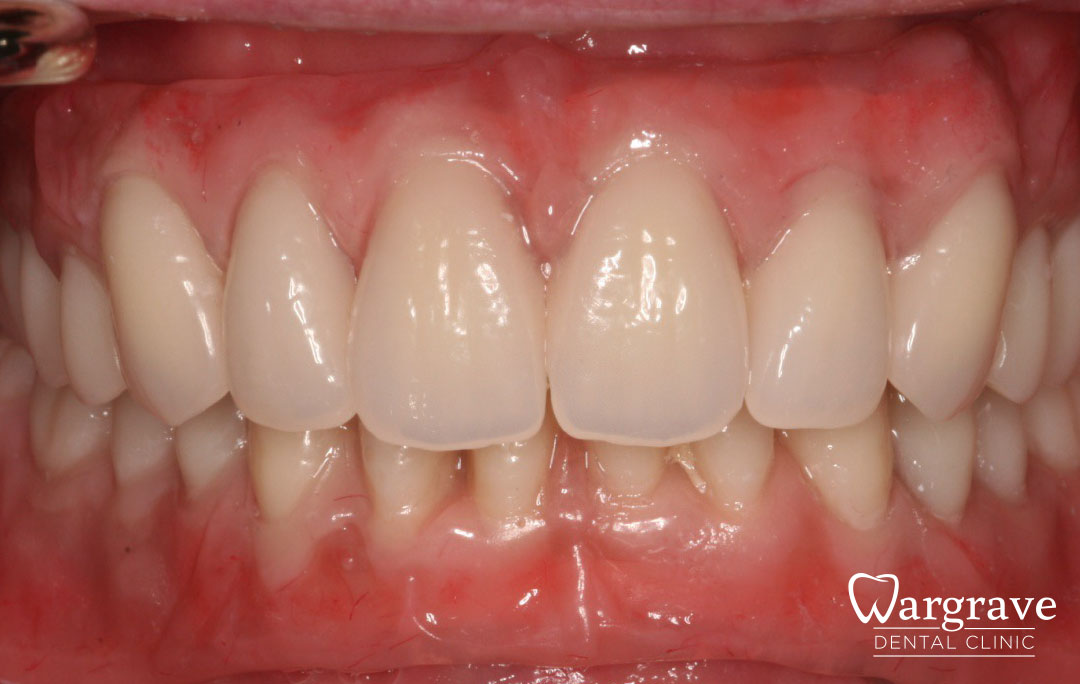

Healthy Smiles These are more advanced examples of different treatments available.All cases shown were carried out by Dr R Khurana unless otherwise stated. Immediate implants Anterior Mandible Bone Regeneration Anterior Mandibular Implant Bridge Maxillary Anterior Implant Bridge Implant stabilised ‘Life Like’ replacement dentures Implant Bridge after 10-years with zero bone loss Implant examples including ZBLC concepts Adhesive Bridge solution for a missing premolar Multidisciplinary care Orthodontics, Replacement veneers and composite bonding Adhesive Bridge solution for missing central incisors Replacement crown, Veneer and Composite Bonding Replacement Crowns and Veneer Injection Moulding using Composite Resin Equilibration Tooth Whitening to treat Developmental Discolouration